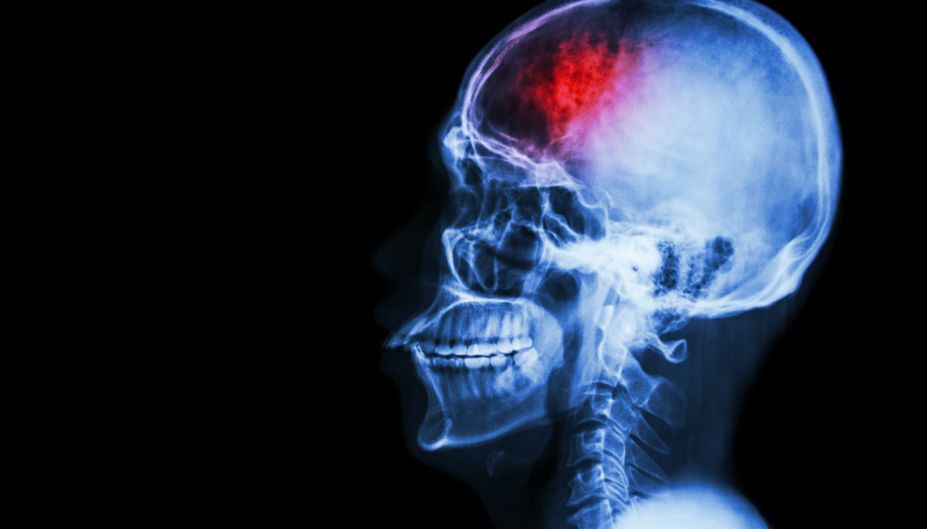

Само не пройдет, скорую немедленно. Развенчиваем мифы об инсульте - Здоровье Mail.Ru